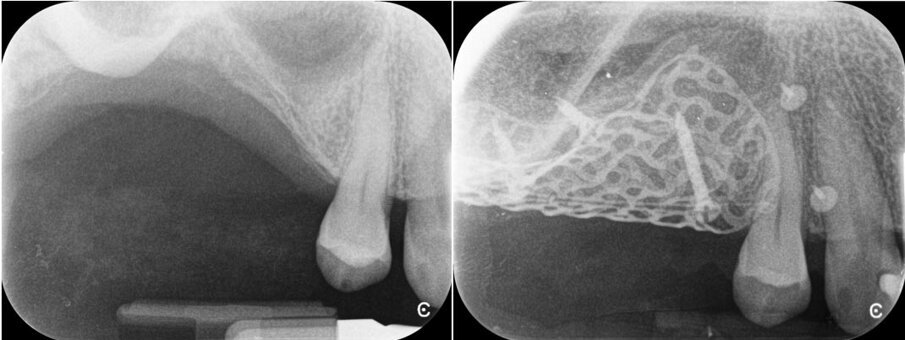

Una paziente di 62 anni, ASA I, non fumatrice e non diabetica, con malattia parodontale precedentemente trattata, si è presentata per una riabilitazione implanto-protesica del mascellare superiore (Fig. 1). L’analisi radiografica, eseguita tramite ortopantomografia (OPT) e tomografia computerizzata cone-beam (CBCT), ha rilevato la presenza di un difetto osseo verticale nel primo sestante, dovuto alla completa perdita del processo alveolare (Figg. 2, 3). Dopo aver discusso con la paziente le possibilità di trattamento, è stato accettato il trattamento proposto come prima scelta, ovvero la ricostruzione ossea del processo alveolare e la successiva riabilitazione mediante corone singole su impianti.

Dopo 14 giorni, sono state rimosse le suture, sono stati raccolti dati relativi al decorso post-operatorio, è stata verificata l’assenza di deiscenze o esposizione o infezione della griglia, ed è stata eseguita una radiografia OPT (Fig. 22). La paziente ha riferito un livello medio di dolore pari a 0, su una scala VAS da 0 a 10, con una media di 1,6 FANS assunti al giorno, durante le prime 2 settimane; inoltre, la paziente ha riferito gonfiore significativo, un piccolo livido esterno sul volto, e la difficoltà ad aprire la bocca. Secondo il questionario Postoperative Symptom Severity (POSSe), si è registrato un valore di 32, indicativo di un moderato disagio postoperatorio.